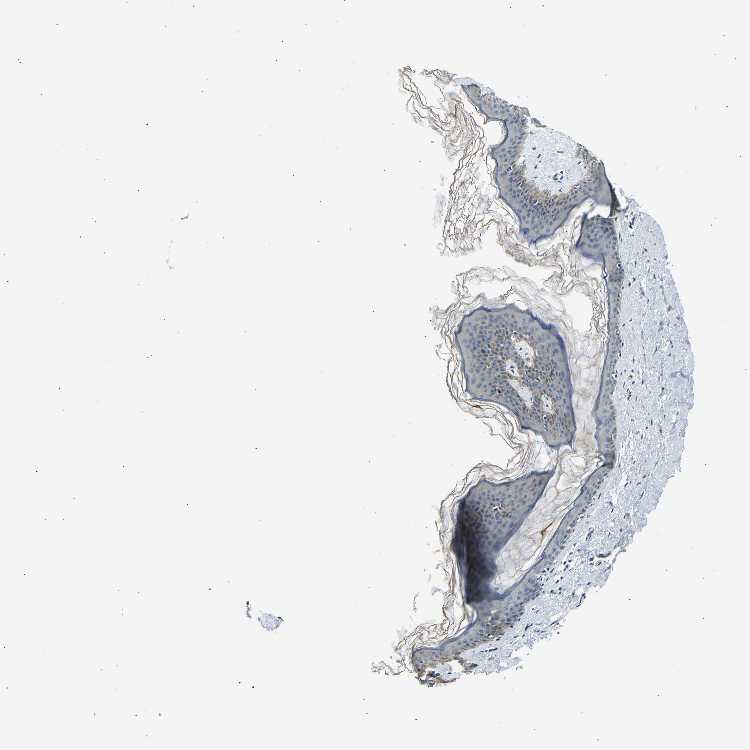

SKIN 1 - Antibody stainingi

Antibody staining in the annotated cell types in the current human tissue is reported as not detected, low, medium, or high, based on conventional immunohistochemistry profiling in selected tissues. This score is based on the combination of the staining intensity and fraction of stained cells.

Each image is clickable and will lead to virtual microscopy that enables deeper exploration of all samples and also displays staining intensity scores, fraction scores and subcellular localization as well as patient and tissue information for each sample.

Antibody HPA013407

Langerhans Not detected

Fibroblasts Low

Keratinocytes Low

Melanocytes Medium